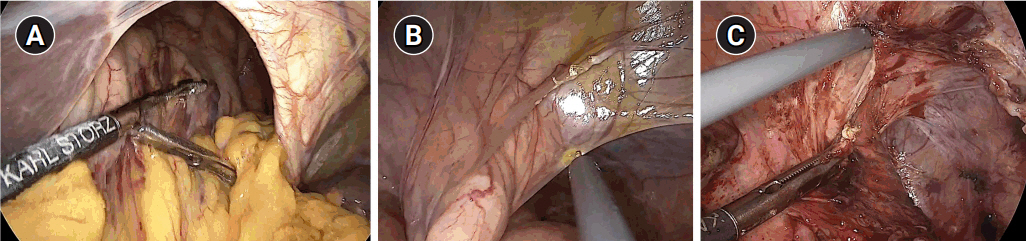

After general anesthesia, laparoscopic exploration (as shown in the video) confirmed that the stomach and transverse colon had been herniated into the thoracic cavity. The ports were positioned similar to those of laparoscopic gastrectomy, but with the operator’s ports placed slightly more medial and upwards (Fig. 2) considering the left-sidedness of the diaphragmatic hernia. Had the diaphragmatic hernia been right-sided, the author would have placed the ports slightly more lateral and lower. Using laparoscopic graspers, the stomach and transverse colon were carefully pulled back into the abdominal cavity (Fig. 3A). Adhesions around the stomach, which were severe most likely due to the chronic herniation, were carefully dissected using a laparoscopic electrode device (Fig. 3B). After meticulous dissection, the stomach was finally mobilized from the thorax and successfully pulled back into the abdominal cavity. Hernia sac was then meticulously dissected, allowing the esophagus to be identified (Fig. 3C). During this procedure, the distal esophagus was injured, creating an iatrogenic hole, which was repaired using 3-0 continuous absorbable barbed suture (Monofix®; Hanmi Healthcare) (Fig. 4). Endoscopic stent or endo-vac therapy, which have been reported to be effective in treating esophageal perforations after paraesophageal hernia operations, was planned to be used postoperatively if necessary [4,5].

Fig. 3.Laparoscopic exploration and reduction. (A) Reduction of the herniated stomach and transverse colon, (B) adhesiolysis around the stomach, and (C) circumferential dissection of the hernia sac.

Fig. 4.Esophageal injury. (A) Iatrogenic injury caused during dissection of the hernia sac. (B) Continuous suture repair using 3-0 Monofix®.